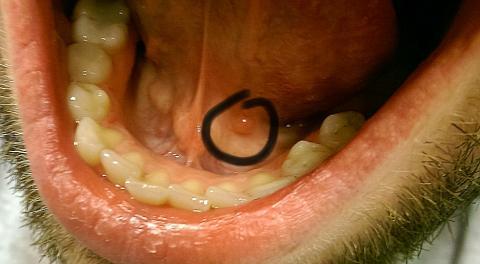

Pro větší náhled klikněte na obrázek

Dobrý deň. Už dlhšiu dobu (asi rok) pozorujem pod jazykom červenú hrčku o veľkosti asi 5mm. Nebolí ma a ani sa nezväčšuje. Prikladám aj fotografiu. Viete mi prosím povedať o čo by sa mohlo jednať ? Ďakujem.

Dobrý den, jde o cystu (tzv. mukokélu), která vznikla ucpáním vývodu malé slinné žlázky v dutině ústní. Ve většině případů zmizí sama, pokud začne dělat obtíže (růst, bolet), navštivte lékaře (stomatolog nebo ORL).